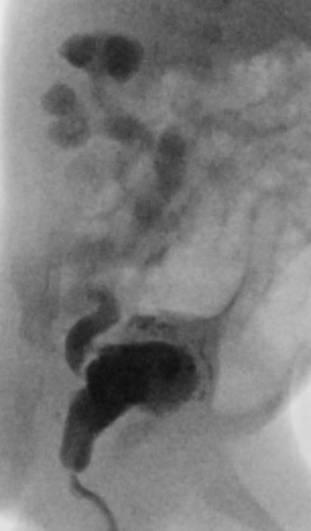

Tijdens de opname zal meerdere keren bloed worden geprikt en zullen er enkele echo’s gemaakt worden. Daarnaast zal via de katheter contrastmiddel in de blaas worden gebracht om met röntgenstraling de urinewegen af te beelden. Dit heet een mictie cystogram. De kleppen kunnen hierop niet worden gezien, maar de verwijding veroorzaakt door de kleppen, de dikke blaaswand en het eventueel terugstromen van urine naar de nieren kan in beeld worden gebracht.

Normale plasbuis voorbij de kleppen

Plaats van de urethrakleppen

Verwijd eerste deel van de plasbuis tot aan de kleppen

Kleine, kramperige blaas met kartelige contour veroorzaakt door uitstulpingen van de blaaswand (divertikels)

Terugstroom van urine tot in de nier (vesico-ureterale reflux) en verwijde urineleider

Plasfoto met contrastmiddel (mictie cystogram)